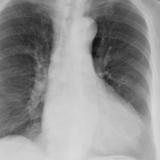

Case 1c

Thymoma